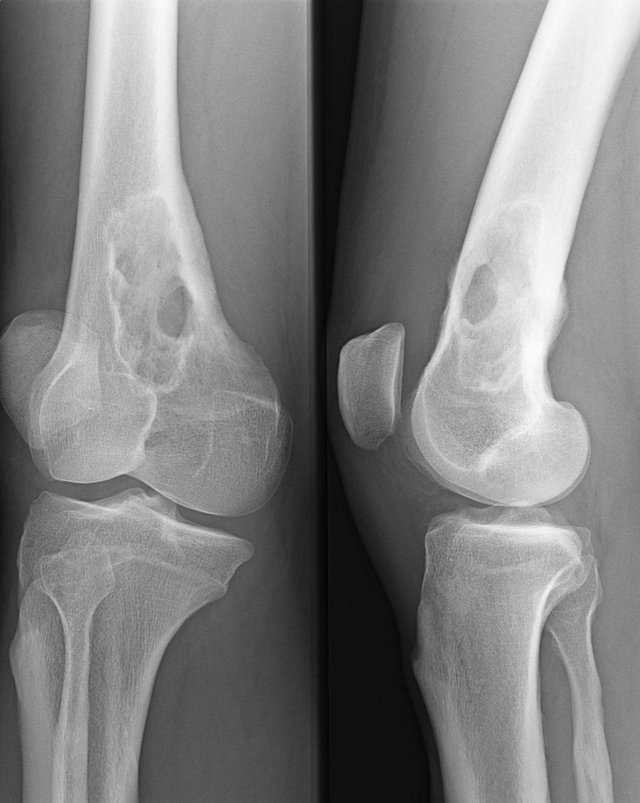

Einen hohen Stellenwert hat beim multiplen Myelom die Labordiagnostik (Differentialblutbild, Nierenwerte, Serumprotein-Elektrophorese etc.). Knochenschäden lassen sich mit der Projektionsradiographie, einem speziellen Röntgenverfahren, oder mit dem Low-dose-Gesamtkörper-CT ermitteln. Die Knochenmarkpunktion dient der zytologischen Sicherung der Diagnose. Genetische Untersuchungen helfen bei der Einschätzung der Prognose und bei der Wahl der geeigneten Therapie.

Bildgebung

Pathologische Fraktur der Elle © wikipedia.org/Hellerhoff, CC BY-SA 3.0